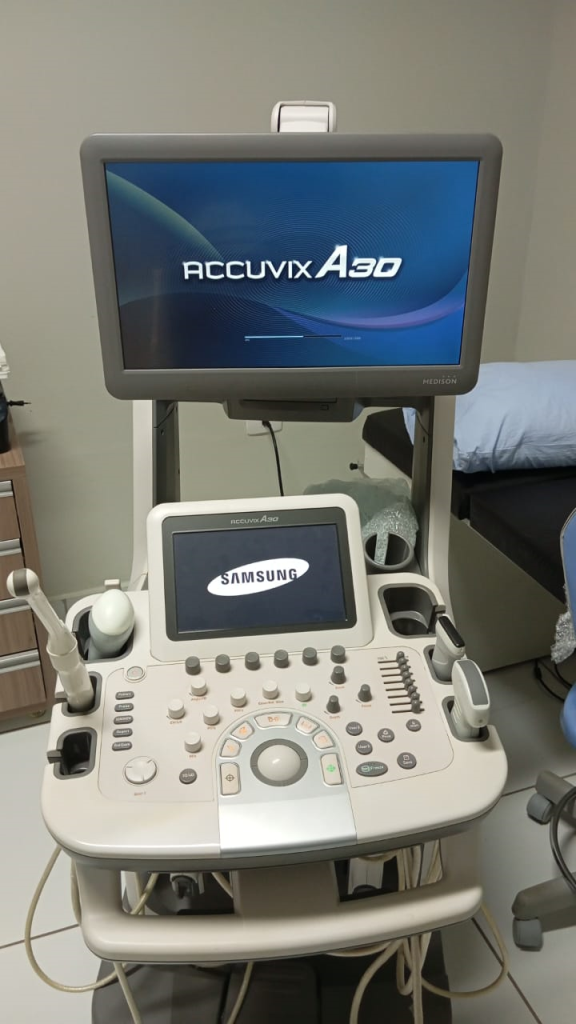

Sistema de Ultrassom Samsung A30

Preço: R$ 70.000,00

- SKU: 65456789

- Condição: Semi Novo

- Fabricante: Samsung

- Garantia: 3 meses

O Accuvix A30 é um upgrade da Samsung ao já poderoso Accuvix XG, adicionando imagiologia 4D de elevada resolução. Estabelece novos padrões operacionais com funcionalidades como EZ Exam e ElastoScan.